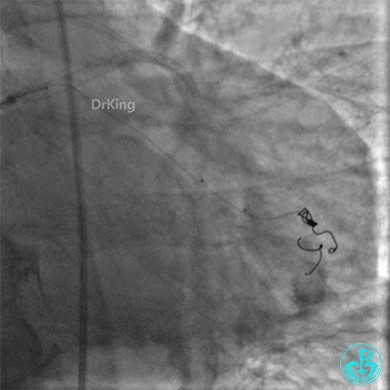

再次上台造影,钝缘支分支远端弹簧圈封堵处仍然有造影剂外漏。

明胶在血管怎么降解并发症丨前降支CTO同侧逆向开通时侧支血管破裂,弹簧圈联合明胶海绵封堵_https://www.jmylbn.com_新闻资讯_第48张

明胶在血管怎么降解并发症丨前降支CTO同侧逆向开通时侧支血管破裂,弹簧圈联合明胶海绵封堵_https://www.jmylbn.com_新闻资讯_第49张

心包穿刺引流。

明胶在血管怎么降解并发症丨前降支CTO同侧逆向开通时侧支血管破裂,弹簧圈联合明胶海绵封堵_https://www.jmylbn.com_新闻资讯_第50张

2根导丝进入到钝缘支分支远端,1根导丝送入微导管,另外1根导丝送入2.5×15mm球囊,2.5×15mm球囊远端Marker与微导管齐口(自制OTW球囊),经微导管缓慢推注明胶海绵糊。